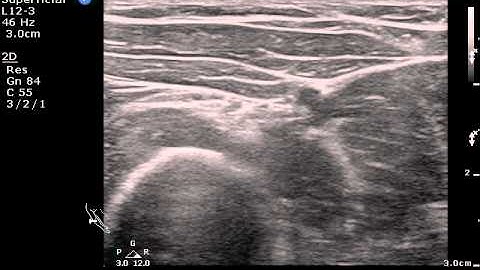

POCUS of the Radial Nerve in the Forearm